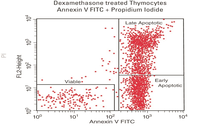

- Evaluation of cell apoptosis by flow cytometry

- Examination of living and dead cells